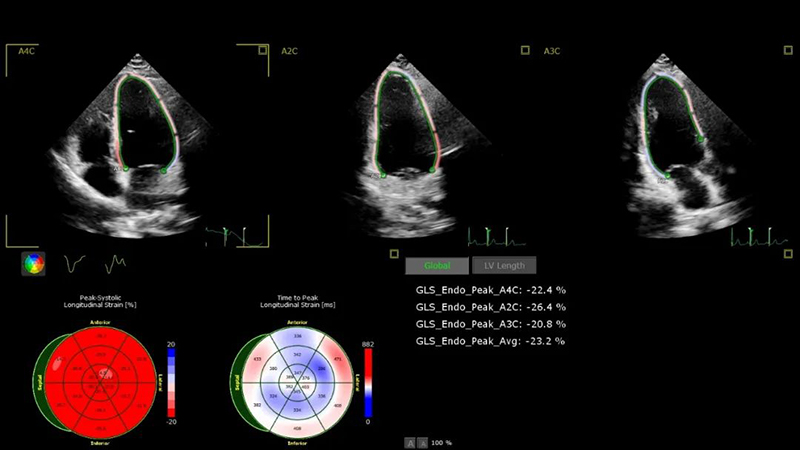

正常的左室心肌應(yīng)變圖